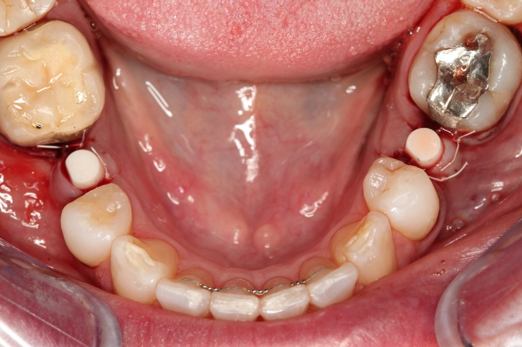

Fig 1. Preoperative surgery.

Figure 1

Figure 1 and Figure 2 depict the preoperative image and subsequent removal of three posterior teeth, immediate placement of zirconia-oxide ceramic dental implants, and soft-tissue augmentation with platelet-rich fibrin (PRF) to enhance the soft-tissue architecture surrounding the ceramic implants. The teeth were removed atraumatically and without suture placement. Because the implants were one-piece in stature (the abutment was incorporated into the implant), the recommendation was to splint the multiple units to minimize the lateral forces from mastication, swallowing, and tongue movement.